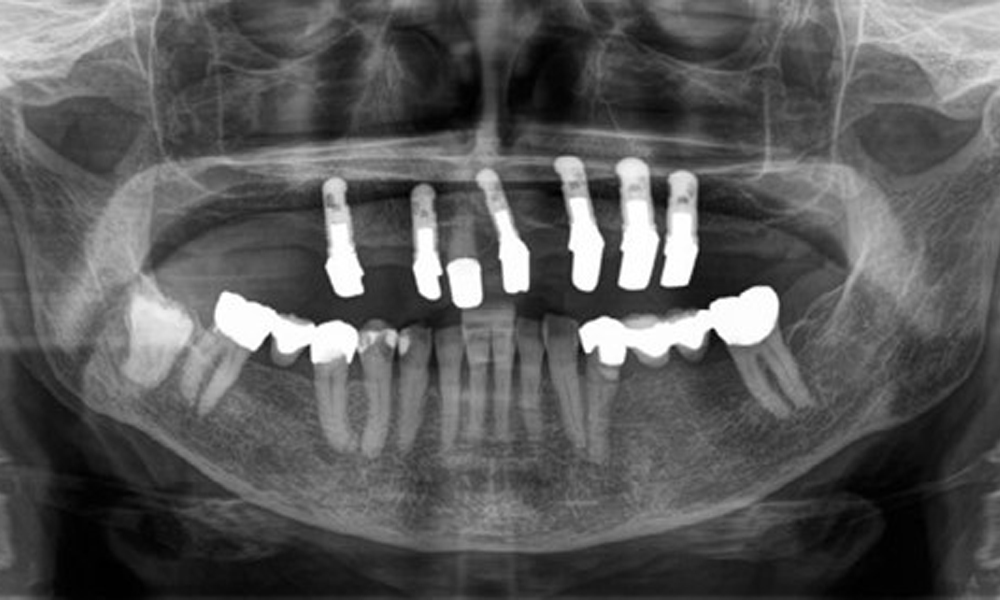

The dental findings are as follows: Combined removable implant and tooth-supported telescopic prostheses on implants 15, 13, 21, 23, 24, 25 and tooth 11 (Fig. 1, Fig. 2, Fig. 3). The patient was fitted with a fixed mandibular denture. Adequate bridges were present over 37 to 34 and 45 to 47 (Fig. 4), the crown margins were intact and there were no active caries. A composite filling with a marginal gap was present on tooth 43. There was mandibular gingival recession, exposing 1 to 3 mm of root surface. This also applies to 11.

The radiological findings show partially edentulous dentition with maxillary implants for teeth 15, 13, 21, 23, 24, 25 and a telescopic crown on tooth 11. Adequate mandibular bridges spanning 37 to 34 and 45 to 47 are present. 48 is impacted. There are suspected secondary caries distally on 43 and mesially on 44. 44 is restored with a non-radiopaque cavity lining. There is generalised horizontal bone loss of approx. 10% to 30% and localised vertical bone loss affecting teeth 22 and 42 (Fig. 5).